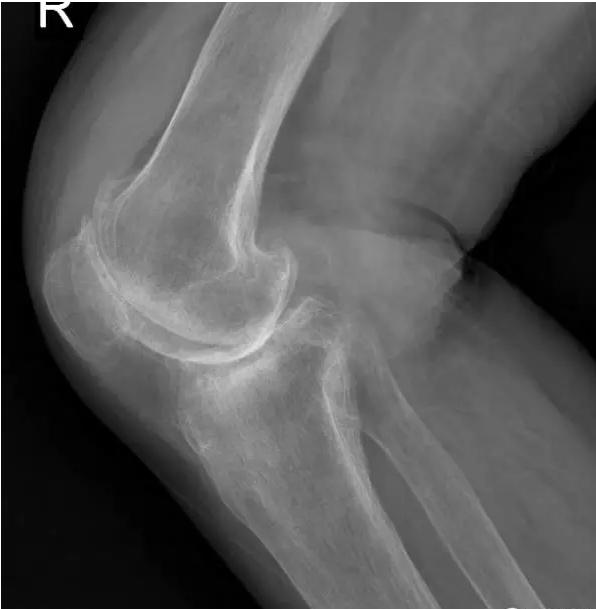

晚期:骨关节炎表现为膝关节明显疼痛,休息后常无缓解,伴有活动受限,可并发畸形,X 线片可见关节周围有明显的骨赘形成,或可见游离体,关节间隙明显狭窄,甚至消失。

术前片: